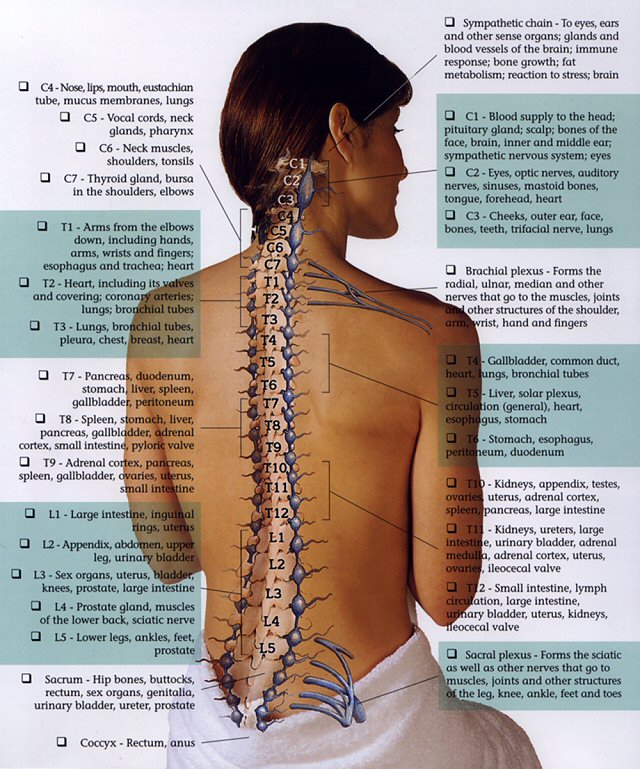

YOUR SPINAL COLUMN – Back To Life Chiropractic

Bones-of-the-Spine-for-EMS – Handley Law

Pin by Michelle Evans on med school | Spinal cord, Spinal nerves …

Diagram | Spinal Cord Injury | Pinterest | Spinal Cord Injury and Cords

Diagram showing the relationship between spinal nerve roots and …

Pin on A&P – CNS

Pin by Allison Atwill on OT Grad in 2021 | Spinal cord, Spinal cord …

spine+diagram | SPINAL NERVES & EFFECTS CHART | Nursing | Anatomia y …